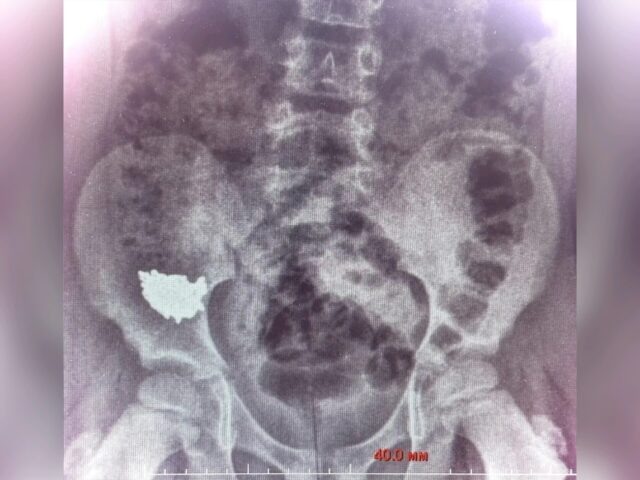

В Воронеже ребёнок случайно проглотил 20-сантиметровую цепочку: ему потребовалась операция

Фото: пресс-служба министерства здравоохранения региона

Сначала малыша госпитализировали, назначили наблюдение и консервативное лечение. Но контрольные снимки на третьи и четвёртые сутки показали, что инородное тело застряло в правой подвздошной области и напрочь отказалось двигаться по ЖКТ. Дальше ждать было нельзя — высок риск воспаления или образования отверстия.